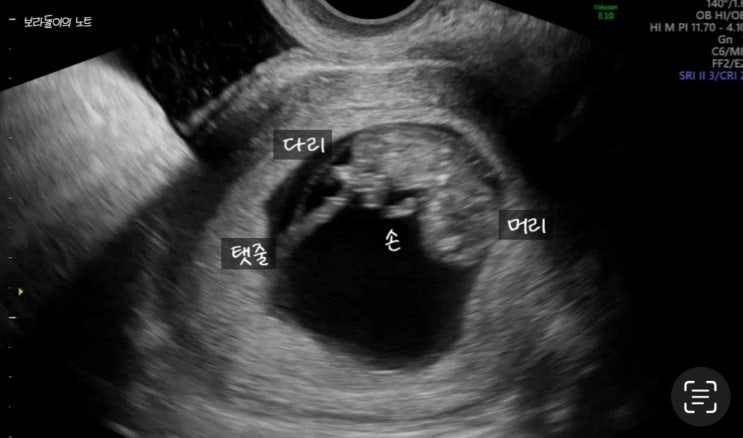

임신12주 입체초음파 첫 확인! 성별 너무 궁금하다 집착하게 된다

어제는 연차를 내고 땡큐 12주 입체초음파를 보러 병원에 다녀왔다. 기형아 선별검사 1차 피검을 했는데, 2...